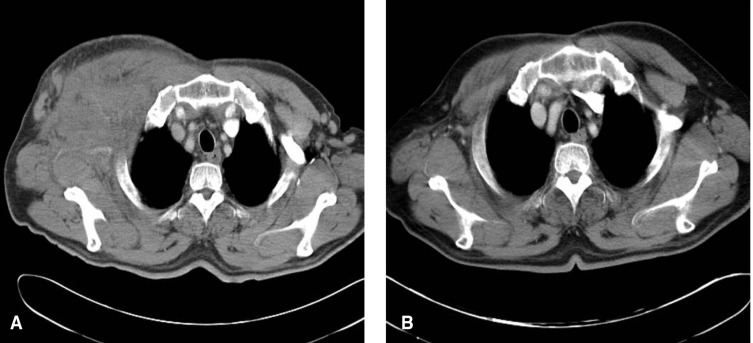

A 67-year-old male was admitted to our hospital because of a protruding swollen chest wall mass on his right side, and he had noticed this mass for 1 month. He also had a complaint of night sweats. His past medical history included an electrical burn about 30 years ago and herpes zoster four months prior to this admission. Serological HIV positivity was detected four months ago while he was being treated for his herpes. His HIV infection was assumed to be transmitted through blood transfusion. He denied ever having homosexual contact or drug abuse. He was on zidovudine, lamivudine and lopinavir. On admission, his blood pressure was 120/80 mmHg, the pulse rate 68/min, the respiration rate 18/min and the body temperature was 36.2℃. The patient appeared generally well on physical examination. The heart and lungs sounds were normal. A chest wall mass measuring 15 cm × 18 cm in diameter was palpable on the right side of his chest. The laboratory finding were as follows: hemoglobin 12.2 g/dL, WBC 6,990/mm3 (neutrophils: 36.5%, lymphocytes: 52.5% and monocytes: 8.9%), platelets 131,000/mm3, ESR 8 mm/h, AST 37 IU/L, ALT 22 IU/L, total bilirubin 0.55 mg/dL, LDH 2,024 IU/L, protein 6.5 g/dL, albumin 3.5 g/dL, BUN 13.7 mg/dL, creatinine 1.2 mg/dL, calcium 7.6 mg/dL, phosphorus 3.4 mg/dL, Na 139 mmol/L, K 4.3 mmol/L, the total number of CD4 and CD8 T lymphocytes was 317/mm3 and 3,085/mm3, respectively, and the ratio of CD4/CD8 was 0.1. The chest X-ray was unremarkable except for marked soft tissue swelling of the right chest wall. The initial chest CT (Figure 8A) showed extensive heterogeneously infiltrative lesions that involved the right side of the chest wall musculature with accompanying edematous change of the overlying skin and subcutaneous layer. The microscopic finding of the mass showed a starry-sky pattern with diffuse proliferation of small to medium sized neoplastic cells (Figure 9A). Immunohistochemical examination showed positivity for CD20 (Figure 9B). The pathological diagnosis was Burkitt's lymphoma. The patient received 4 cycles of dose adjusted EPOCH regimen (a 4-day infusion of etoposide 50 mg/m2, doxorubicin 10 mg/m2 and vincristine 0.4 mg/m2 with dose-adjusted cyclophosphmide 375 mg/m2 on day 5 and prednisone 60 mg/m2 for 5 days) every 3 weeks. Granulocyte colony-stimulating factor was used uniformly, beginning at day 6, and all HAART was withheld until day 6 of the last dose of chemotherapy. The soft tissue lesion responded very well to chemotherapy. The chest wall mass decreased in size after the first cycle of chemotherapy. After four cycles of chemotherapy, follow-up CT revealed marked regression of the lymphoma in the right chest wall (Figure 8B). He is currently alive and well in a state of complete remission of the lymphoma for more than 18 months.

(A) The initial chest CT shows extensive heterogeneously infiltrative lesions involving the right side of the chest wall musculature with the accompanying edematous changes of the overlying skin and subcutaneous layer. (B) After 4 cycles of chemotherapy, the follow-up MRI revealed marked regression of the lymphoma in the right chest wall.